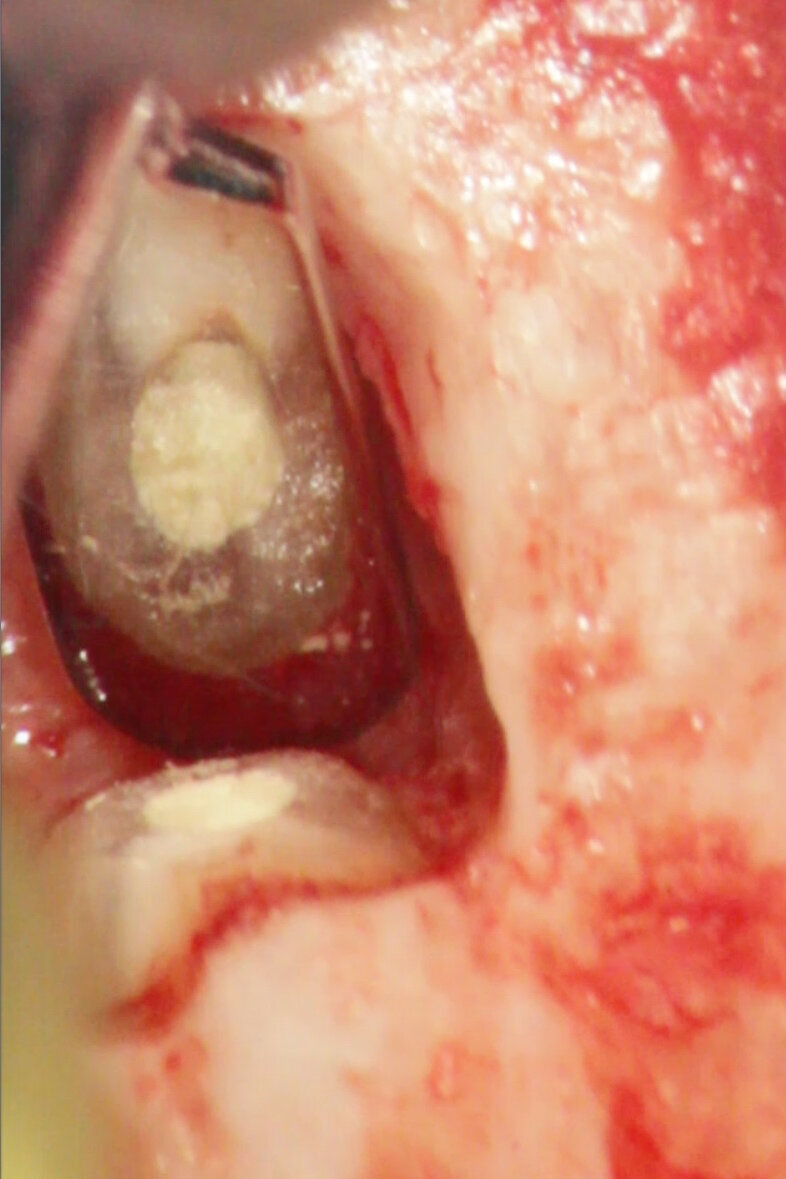

Apical surgery

MTA is the material with the most favourable outcome as a root-end filling material for apical surgery. MTA has been associated with significantly less inflammation, cementum formation over MTA and regeneration of the periradicular tissue (Figs. 4a–f).[2]

Fig. 4a: (a) Pre-op radiograph with a large periradicular lesion. (b) Periapical surgery. (c) MTA application with the MAP System and PD MTA White. (d) Condensation of the MTA with pluggers. (e) Mirror view of the root-end cavity filled with MTA. (f) Post-op radiograph showing the root-end filling.

Fig. 4b: (a) Pre-op radiograph with a large periradicular lesion. (b) Periapical surgery. (c) MTA application with the MAP System and PD MTA White. (d) Condensation of the MTA with pluggers. (e) Mirror view of the root-end cavity filled with MTA. (f) Post-op radiograph showing the root-end filling.

Fig. 4c: (a) Pre-op radiograph with a large periradicular lesion. (b) Periapical surgery. (c) MTA application with the MAP System and PD MTA White. (d) Condensation of the MTA with pluggers. (e) Mirror view of the root-end cavity filled with MTA. (f) Post-op radiograph showing the root-end filling.

Fig. 4d: (a) Pre-op radiograph with a large periradicular lesion. (b) Periapical surgery. (c) MTA application with the MAP System and PD MTA White. (d) Condensation of the MTA with pluggers. (e) Mirror view of the root-end cavity filled with MTA. (f) Post-op radiograph showing the root-end filling.

Fig. 4e: (a) Pre-op radiograph with a large periradicular lesion. (b) Periapical surgery. (c) MTA application with the MAP System and PD MTA White. (d) Condensation of the MTA with pluggers. (e) Mirror view of the root-end cavity filled with MTA. (f) Post-op radiograph showing the root-end filling.